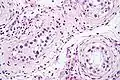

| Intratubular germ cell neoplasia. H&E stain. | |

GCNIS is not palpable, and not visible on macroscopic examination of testicular tissue. Microscopic examination of affected testicular tissue most commonly shows germ cells with enlarged hyperchromatic nuclei with prominent nucleoli and clear cytoplasm. These cells are typically arranged along the basement membrane of the tubule, and mitotic figures are frequently seen. The sertoli cells are pushed toward the lumen by the neoplastic germ cells, and spermatogenesis is almost always absent in the affected tubules. Pagetoid spread of GCNIS into the rete testis is common. Immunostaining with placental alkaline phosphatase (PLAP) highlights GCNIS cell membranes in 95 percent of cases. OCT3/4 is a sensitive and specific nuclear stain of GCNIS.[3]

ITGCN. H&E stain.